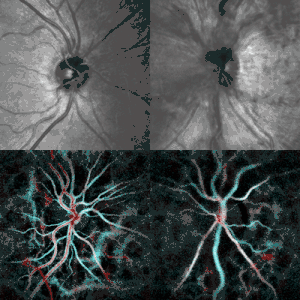

-

Papilledema (right) revealed by scanning laser ophthalmoscopy (top) and laser Doppler imaging (bottom). Healthy contralateral eye (left). -

Fundal photograph showing severe papilloedema in the right eye.